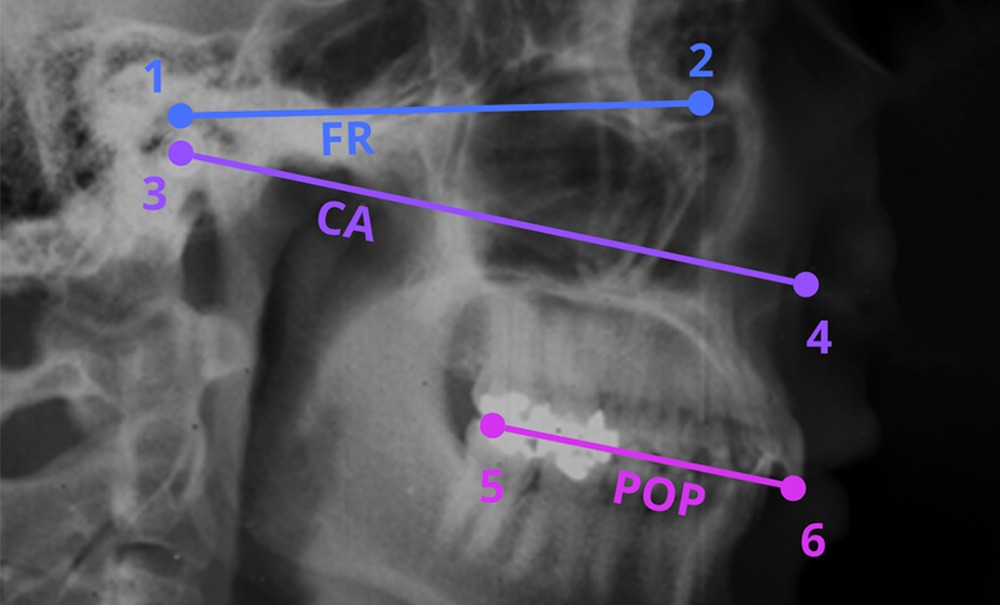

La mise en œuvre d’un traitement prothétique implique la collecte de données biologiques (fonctionnelles et esthétiques), afin de créer une reproduction individualisée mais partielle du système manducateur [1-4]. Cette individualisation du traitement prothétique repose donc sur des dispositifs techniques de simulation, conventionnels tels que les articulateurs dentaires [1-3], ou digitaux dans le cas de simulateurs numériques [5, 6]. Comme dans tout dispositif de simulation d’un système biologique complexe, les paramètres d’entrée du simulateur sont soumis à des biais de mesures ou d’échantillonnage pouvant impacter les paramètres de sortie [7, 8].

Dans le cadre de la simulation du système manducateur en réhabilitation oro-faciale, cela implique qu’il peut exister des erreurs de mesures lors de la collecte des déterminants esthétiques et fonctionnels pouvant compromettre la correcte reproduction de la position des arcades maxillaire et mandibulaire et de leur cinématique [9, 10]. Une quantification de ces erreurs de mesures apparaît alors essentielle afin de valider cliniquement l’utilisation d’un simulateur ou de tout autre type de dispositif médical impliquant la collecte de données biologiques [11]. Dans le cadre de cette quantification, la variabilité intra-observateur définit la variabilité d’une mesure lorsque le même observateur reproduit la collecte de données dans des conditions similaires, standardisées et sur le même objet d’étude [11]. La variabilité inter-observateur élargit le concept en définissant la variabilité existant entre deux observateurs ou plus pour la même mesure, sur le même objet d’étude dans des conditions similaires et standardisées [11]. La reproductibilité (intra ou inter-observateur) constitue alors le concept complémentaire de la variabilité : ainsi lorsque la variabilité d’une mesure augmente, sa reproductibilité diminue [11].